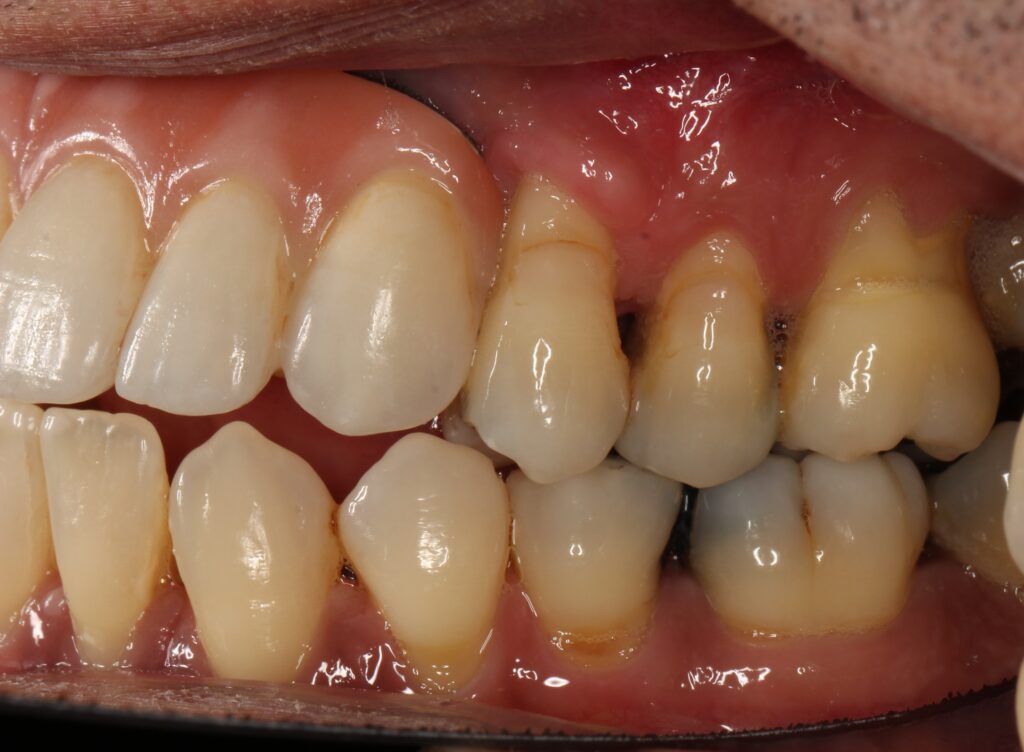

A selection of partial arch fixed implant bridge patients